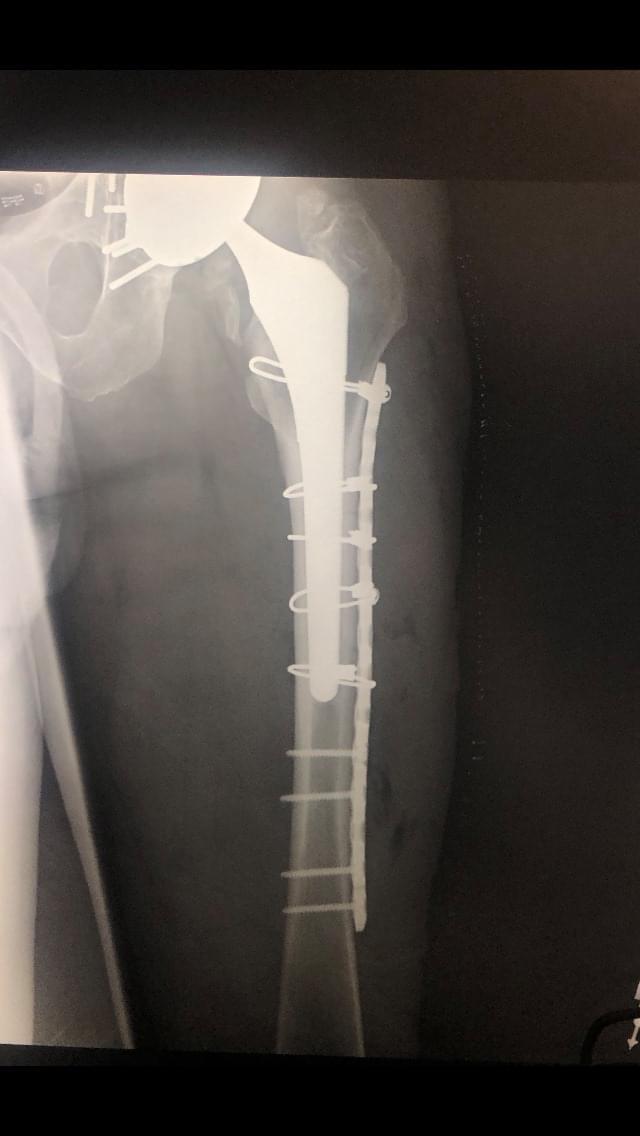

Periprosthetic Femur Fracture ORIF, Stem Revision What Is A Spiral Femur Fracture In this type of fracture, the bone is in at least two pieces, and. This type of broken leg almost always requires surgery to heal. The bone is broken into three or more pieces. The break has a line that encircles the shaft like the stripes on a barber pole or candy cane. Treatment can depend on the severity of. What Is A Spiral Femur Fracture.